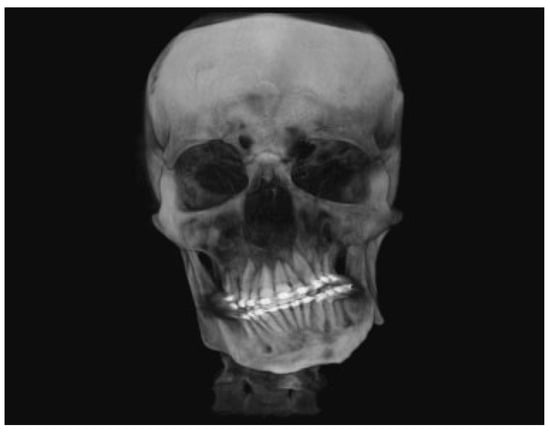

:Case Report